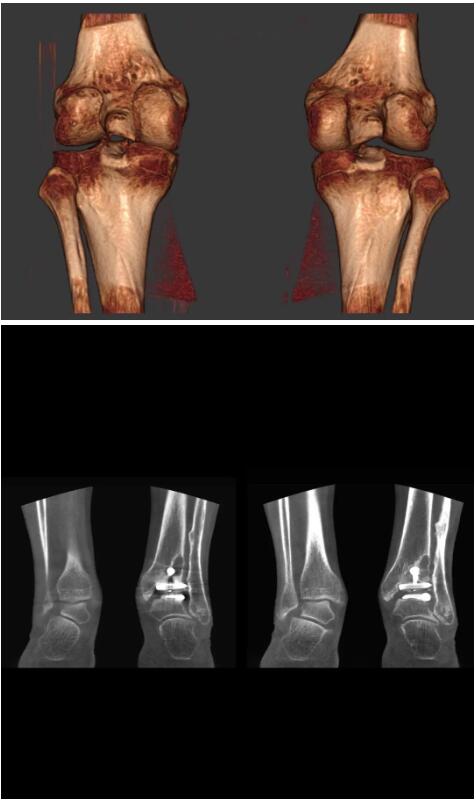

另外一款被稱(chēng)為世界上最小的CT,它的重量?jì)H300磅,不僅能夠掃查足部,還可以檢查膝蓋和上肢等。

與上面介紹的CT一樣,它同樣具有輻射低、占地空間?。?3*36)的特點(diǎn),隨開(kāi)隨用(支持直接接入墻上的插座)。

這款CT使用非常方便,通過(guò)上下移動(dòng)保持與患者的手臂或者雙腿齊平,掃描快速,僅需要30秒左右就可以完成掃查。

以上介紹的CT均來(lái)自國外同一家公司,這些CT均配置了可視化軟件,可以進(jìn)行切片、3D重建以及大型CT附帶的所有典型的操作功能。

以下是這些“特立獨行”的CT所拍出來(lái)的圖像: